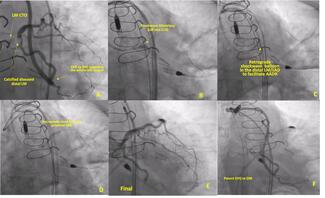

Jonathan Davis, MD; Emmanouil S. Brilakis, MD, PhD, FACC, FAHA, FESC, FSCAI; Michael S. Megaly, MD, MS; Khaldoon Alaswad, MD

A 72-year-old woman presented with progressive angina and anterior ischemia on a nuclear stress test.